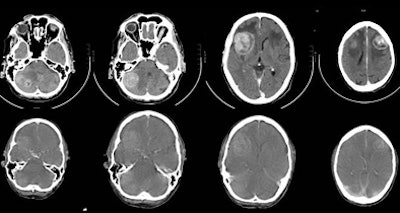

| A 67-year-old man with small cell lung cancer in the left upper lobe also developed neurological symptoms. Diagnostic brain CT (upper row) showed multiple brain metastases: two right cerebellar, one right frontal, and one left frontal, all surrounded by edema. The CT component of the integrated PET/CT (lower row) also showed brain metastases but could not demonstrate one right cerebellar metastasis (first image). The quality of the CT of the PET/CT is inferior to that of diagnostic brain CT. There is reduced contrast opacification and the surrounded edema is not clearly visualized, although this could have been due to the treatment with corticosteroids in the short time between diagnostic brain CT and integrated PET/CT. All images and charts courtesy of Dr. Walter De Wever. |